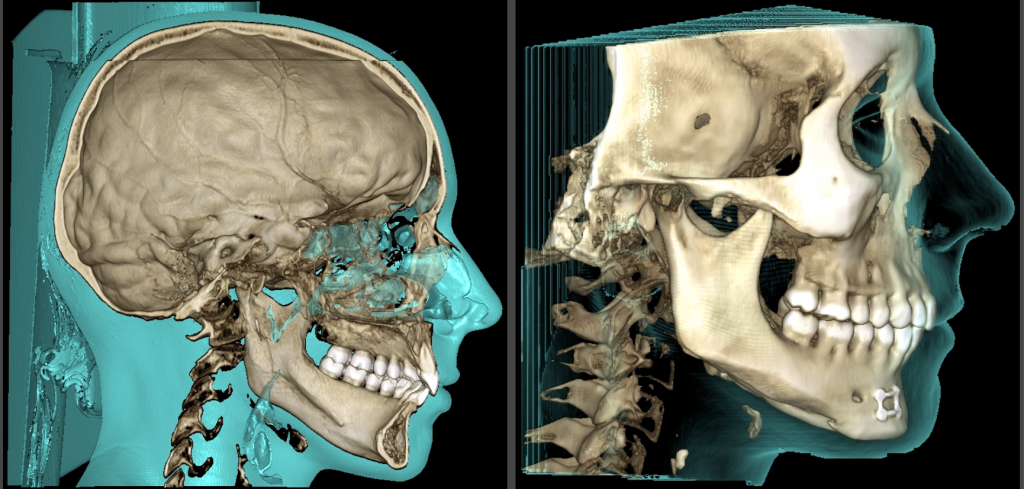

Découvrez les photos et le scanner avant/après pour observer l’évolution spectaculaire de ce cas de malformation oto-mandibulaire unilatéral Gauche.